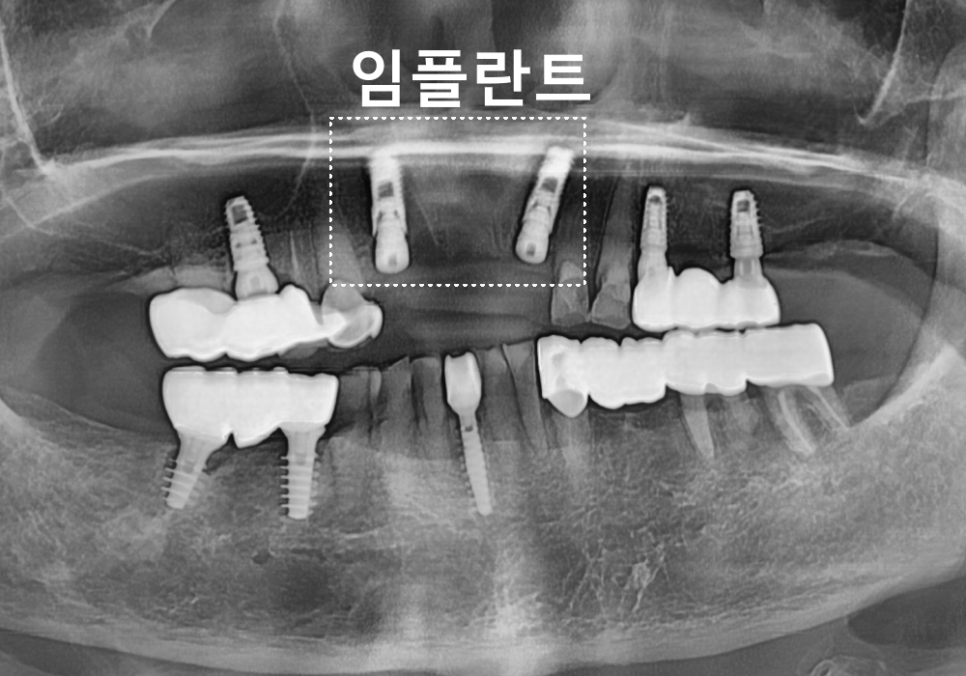

240408

다행히 CT에서 확인했을 때

뼈의 높이와 두께가 비교적 괜찮아

뼈이식 없이 임플란트를

식립할 수 있었습니다.

치유 기간을 거쳐

약 3개월 뒤

최종 보철까지 완성했습니다.

240709

그 후 1년이 지나고...

심한 충치로 인한 치아 부러짐, 상일동 임플란트로 해결한 사례

해놓은 임플란트는 잘 쓰고 계셨는데,

이번에는 임플란트 옆 치아인,

오른쪽 위 치아(#13, #14)가

부러져 내원하셨습니다.

250503